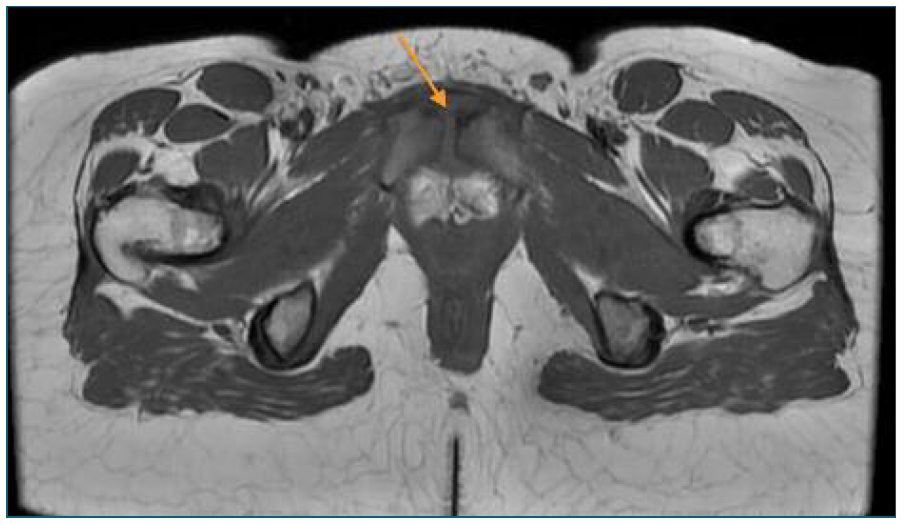

For this reason, a computed tomography (CT) was performed and showed pre-pubic soft tissues higher density and intra-articular air in the symphysis pubis (Figure 1), which led to suspicion of an osteitis. A magnetic resonance imaging (MRI) confirmed the diagnosis by showing hyperintense T2 signal and cortical irregularities on the articular surface associated with few intra-articular fluid and densifications of the soft tissues (Figures 2 and 3). At the same time, blood cultures were positive for Streptoccocus Anginosus and a puerperal osteomyelitis pubis was assumed. Antibiotic therapy was changed to intravenous benzylpenicillin (24 million Units per day), according to the antibiogram. Considering the high diagnostic certainty, based on clinical and imagological features, and technical difficulties, an aspirative biopsy was not performed. In consideration to Streptoccocus Anginosus found on blood cultures, the patient was submitted to an echocardiogram that excluded any sign of endocarditis.

Figure 2 Pelvic MRI (axial plane) - MRI showing hyperintense T2 signal and cortical irregularities on the articular surface and densifications of the soft tissues.